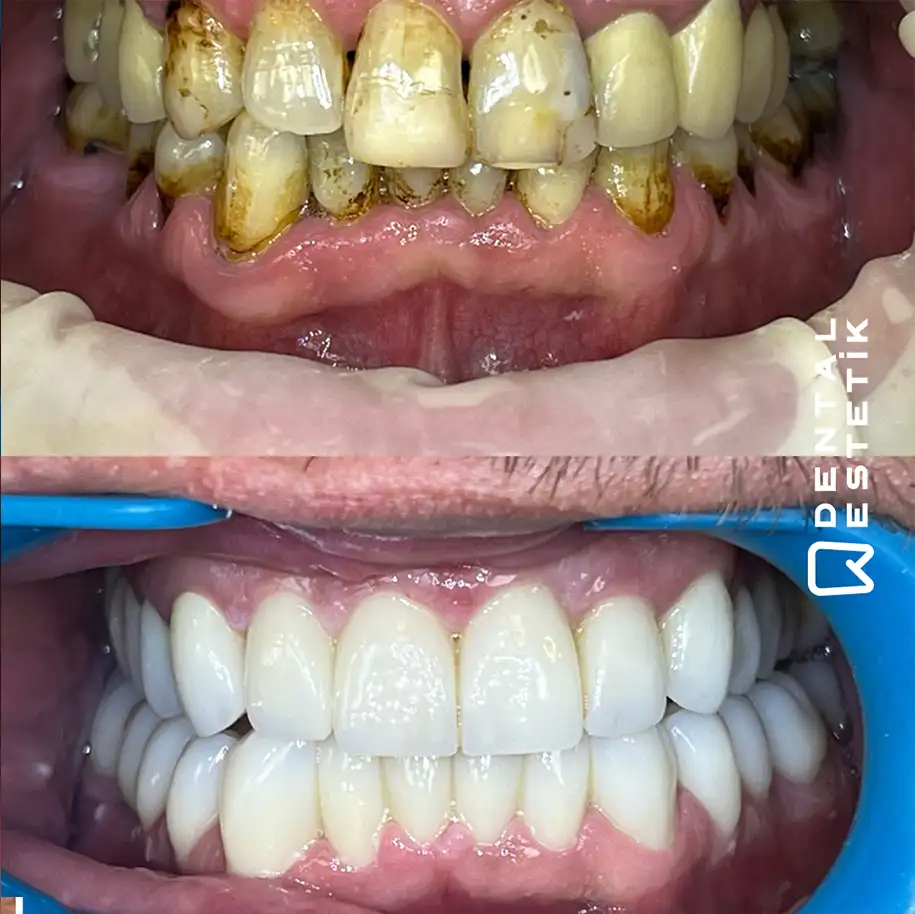

Dental Estetik Ağız ve Diş Sağlığı Polikliniği is a leading dental clinic located in Manisa, Turkey, committed to providing exceptional dental care with a focus on patient comfort and satisfaction. With over 15 years of experience and approximately 10,000 patients served, the clinic boasts a team of expert dentists, including Dt. Tuncer ÖZTÜRK, Dt. Recep SEVER, and Dt. Reyhan DİRMİLLİ, who utilize state-of-the-art technology such as CAD/CAM and 3D printing to deliver high-quality results. The clinic's comprehensive range of treatments includes dental implants, professional teeth whitening, root canal treatments, and specialized solutions like the All-on-Four and All-on-Six implant techniques, which offer innovative options for patients who have lost most or all of their teeth. In addition to its advanced dental services, Dental Estetik also provides a complete health tourism package, ensuring a hassle-free experience for international patients. This includes round-trip airfare, airport transfers, luxurious accommodations, and all essential dental treatments, allowing patients to focus solely on their health and well-being. The clinic emphasizes a patient-centered approach, crafting personalized treatment plans tailored to individual needs, and ensuring that every visit is a step towards achieving a confident and healthy smile.